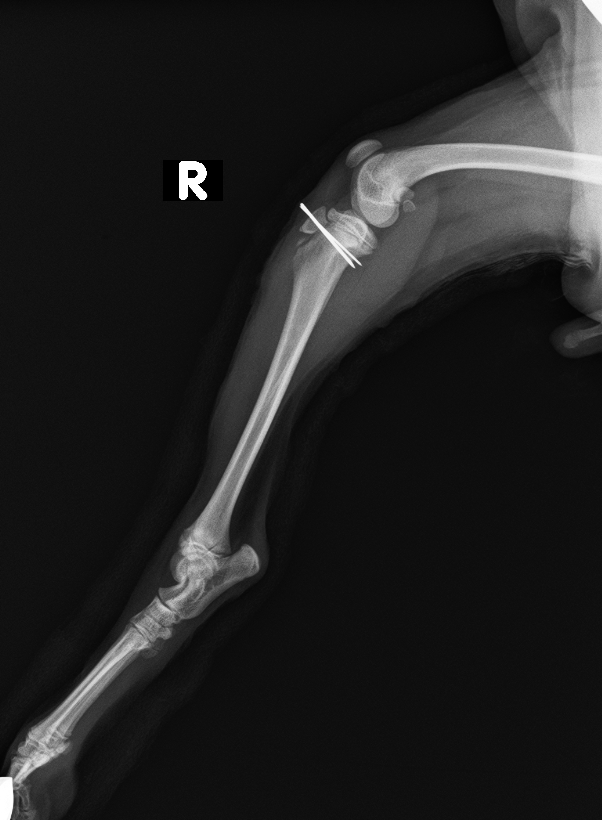

脛骨粗面にKワイヤーを挿入して固定

after